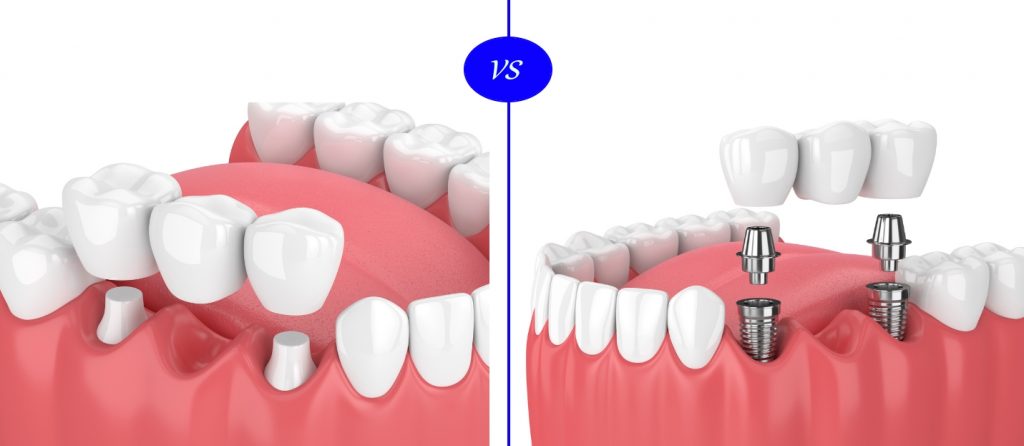

ایمپلنت در اصل جایگزین ریشه دندان شما می شود، ایمپلنت یک پایع قوی و مستحکم برای دندان ثابت (دائمی) و یا قابل جابجایی می باشد که در عین حال با دندان های طبیعی سازگاریه بالایی دارد.

جنس ایمپلنت دندان از تیتانیوم خالص می باشد که بزرگترین مزیت آن سازگاری با بدن انسان می باشد و به صورت یک میله باریک می باشد که درون استخوان فک تعبیه می شود. البته بیشتر متخصصین دندان پزشکی بر این باور می باشند که ایمپلنت دندان بهترین و در عین حال با کیفیت ترین جایگزین برای دندان هایی که خراب شده اند می باشد و نکته قابل توجه در مورد ایمپلنت دندان این می باشد که اگر به طور صحیح و درست از آن حفاظت و نگهداری شود طول عمر و ماندگاری زیادی دارند و همین نکته باعث شده است که مورد توجه اکثر مردم قرارگیرد.

اندوستیال و سابپریوستیال. ایمپلنت نوع اول درون استخوان فک کاشت می شود. ایمپلنت نوع دوم روی استخوان آرواره و همچنین زیر بافت لثه جایگزاری می شود.